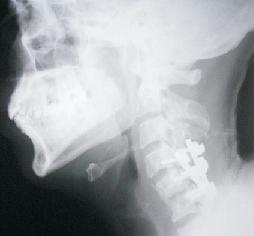

Odantoid Fracture

Facet Dislocation

Tubercular Spondilytis

Cervical Vertebral Fracture

Vertebral Injury

Cervical Cord Compression